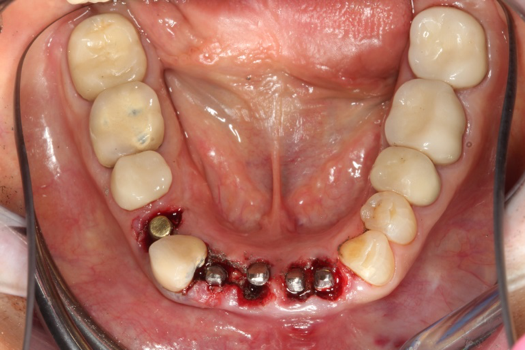

The next case follows the digital protocol for fully guided surgery and prosthetics. A CBCT radiograph, digital impression, and digital photography were the cornerstones to the success of this case. The 3D data set was electronically delivered to the dental laboratory. The data were merged and the process to develop the plan was initiated. The use of CBCT was essential in this case, particularly due to minimal space for placement of individual implants and single-unit crowns. The patient's chief concern was that she wanted to have single-unit crowns instead of fixed crown-and-bridge restorations because she was worried that she would someday find herself in an assisted-living facility; if that were to happen, she wondered, who would help floss under her bridge work? Her decision was to have single implants with individual crowns. CBCT technology is much more accurate in evaluating space maintenance and management.10 Periapicals in the past were rather close for calculating spacing; however, the CBCT identifies the buccal-lingual dimensions as well as the mesial-distal measurements. On review of the completed proposals for implant placement and provisionals, it was determined that there was sufficient spacing for implant placement to allow appropriate emergence profiles for the provisionals and then eventually the final single-unit cemented crowns. The proposal was accepted, and a 3D-printed surgical stent was fabricated, along with the PMMA provisionals (Figure 29 through Figure 35).

On the day of surgery, the plan was to extract teeth Nos. 21, 23, 24, 25, and 26, place 3.0 x 13-mm implants in the anterior region due to limited spacing, and place a 4.1 x 10-mm implant in the No. 21 extraction site. Before the extractions were performed, the No. 23 pontic was sectioned from the existing 2-unit cantilevered bridge utilizing ceramic and metal high speed rotary cutting burs ZR 6881 and H34L (Komet-USA), respectively. After removal of the pontic and extractions, the surgical guide was verified to be seating positively (Figure 36 through Figure 38). Surgical guide protocol was followed, and all implants were successfully placed and torqued to a value of greater than 35 Ncm (Figure 39 and Figure 40). All implants were placed without flapping, with the exception of No. 23. The flap was elevated to reposition lingual keratinized tissue facially for enhanced esthetic tissue profile. The implants were then prepared with a high-speed carbide bur (Komet-USA) with copious amounts of water (Figure 41 and Figure 42). The one-piece 3.0-mm diameter implant served the needs of the patient's spacing requirements. Inter-occlusal space requirements and path of draw were verified. The PMMA provisionals were air abraded and relined with crown-and-bridge material (Figure 43 through Figure 45).

Fig 42. Occlusal view of prepared implants.

Figure 42

Fig 43. PMMA provisional digitally fabricated and milled.

Figure 43

Fig 44. Splinted PMMA seated.

Figure 44

Fig 45. Occlusal view of seated PMMA provisionals.

Figure 45